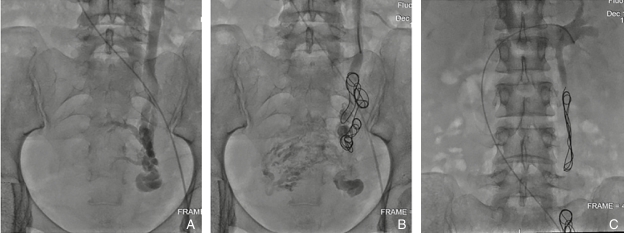

图1 卵巢静脉反流的治疗过程 A:左侧卵巢静脉造影显示重度反流、盆腔静脉迂曲;B:卵巢静脉远端弹簧圈栓塞、注射硬化剂;C:近心端卵巢静脉弹簧圈栓塞,造影显示卵巢静脉反流消失Fig.1 Treatment process of ovarian vein reflux A: Left ovarian vein venography showing severe reflux and tortuous pelvic veins; B: Distal ovarian vein coil embolization with sclerosing agent injection; C: Proximal ovarian vein coil embolization, with venography demonstrating complete resolution of ovarian vein reflux